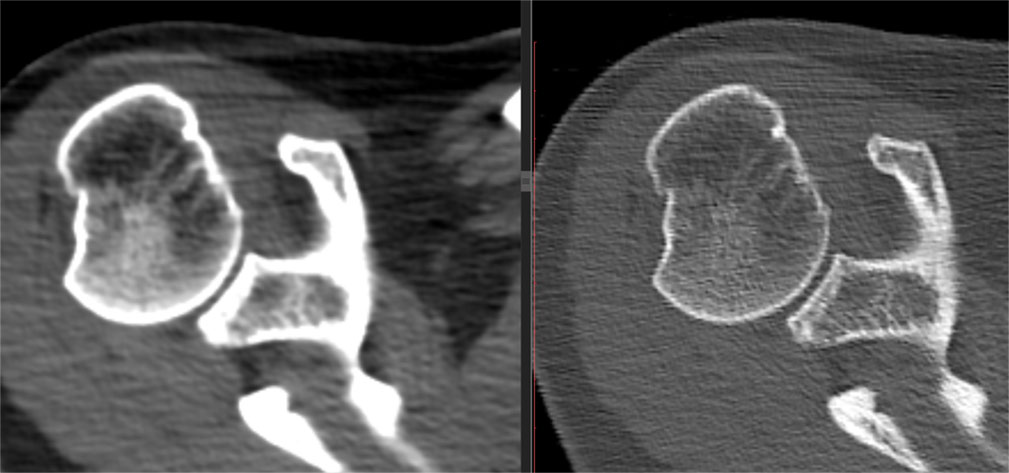

Afișarea cu evidențierea părților moi sau ale osului

Pentru articulații/oase se folosesc de obicei imagini cu două tipuri de parametri diferiți: pentru părți moi și pentru os.

Imaginile cu parametri de părți moi (“kernel” dedicat părților moi) sunt de obicei cu contururi mai line, mai “smooth”, cu “netezirea” artificială a micilor detalii și permit reconstrucții 3D foarte plăcute ochiului, cu aspect anatomic.

Imaginile cu parametri de os (“kernel” dedicat osului) sunt cu conturi mult mai netede, mai exacte, mai “sharp”, care permite o foarte bună apreciere a celor mai fine traiecte de fractură, însă imaginile 3D obținute pe seama acestora nu sunt la fel utile, fiind cu margini ascuțite și un aspect mai puțin plăcut vizual datorită prea multor detalii prezente.

Image

Aspect comparativ - afișarea în fereastră de părți moi (stânga) și în fereastră de os (dreapta)